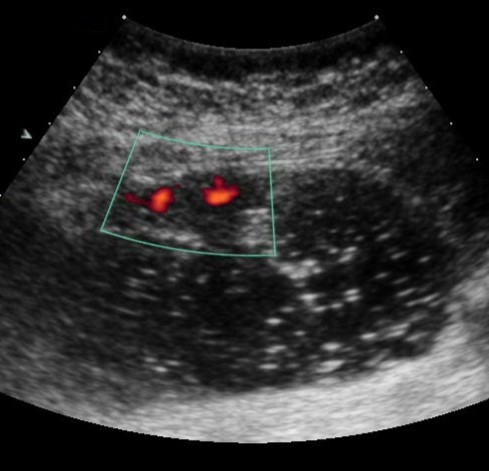

Weak vascularization was manifested in the form of a single point color vascular signals, the moderate vascularization - in the form of linear color vascular signals and the enhanced vascularization - in the form of wide color areas inside the tumor (Figure 16, Figure 17).

Figure 17.Gastric carcinomas of infiltrative ulcerative form of Ts stage. Despite the small size of the tumor the vascularization is manifested in the form of wide color areas inside the tumor.

Metastasis to the regional lymph nodes was diagnosed in 52 cases. Ultrasonographically, this was detected in 37 (71.2%) cases. Sonographic features of lymph node metastatic lesions are: an increase in their thickness, a decrease in echogenicity, deterioration or lack of differentiation of the peripheral and central parts of the nodes, recording of color vascular signals inside the nodes (Figure 18, Figure 19).